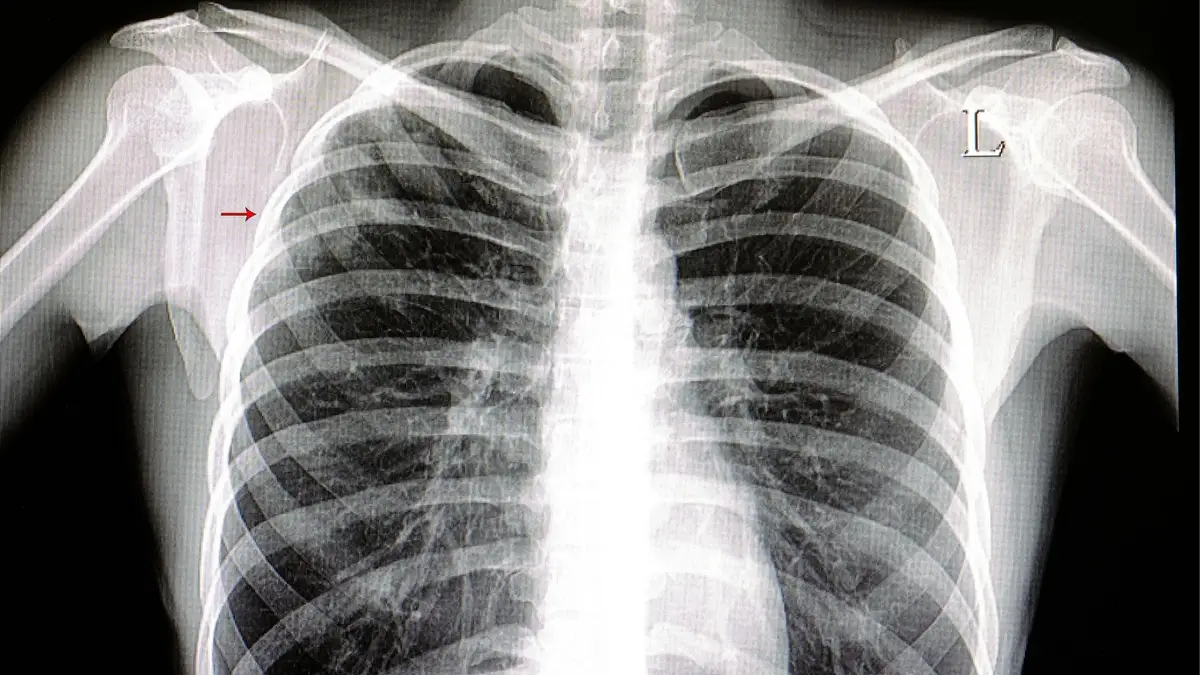

Análises, raios x, TAC ou outros exames realizados em qualquer instituição de saúde vão estar acessíveis a todos os médicos, sejam do serviço nacional de saúde, do privado ou do setor social

Numa primeira fase e segundo o jornal de notícias, os utentes terão acesso a um documento com o relatório médicos do exame realizado mais tarde pretende se que as imagens possam ser descarregadas também facilitando diagnósticos e tratamentos